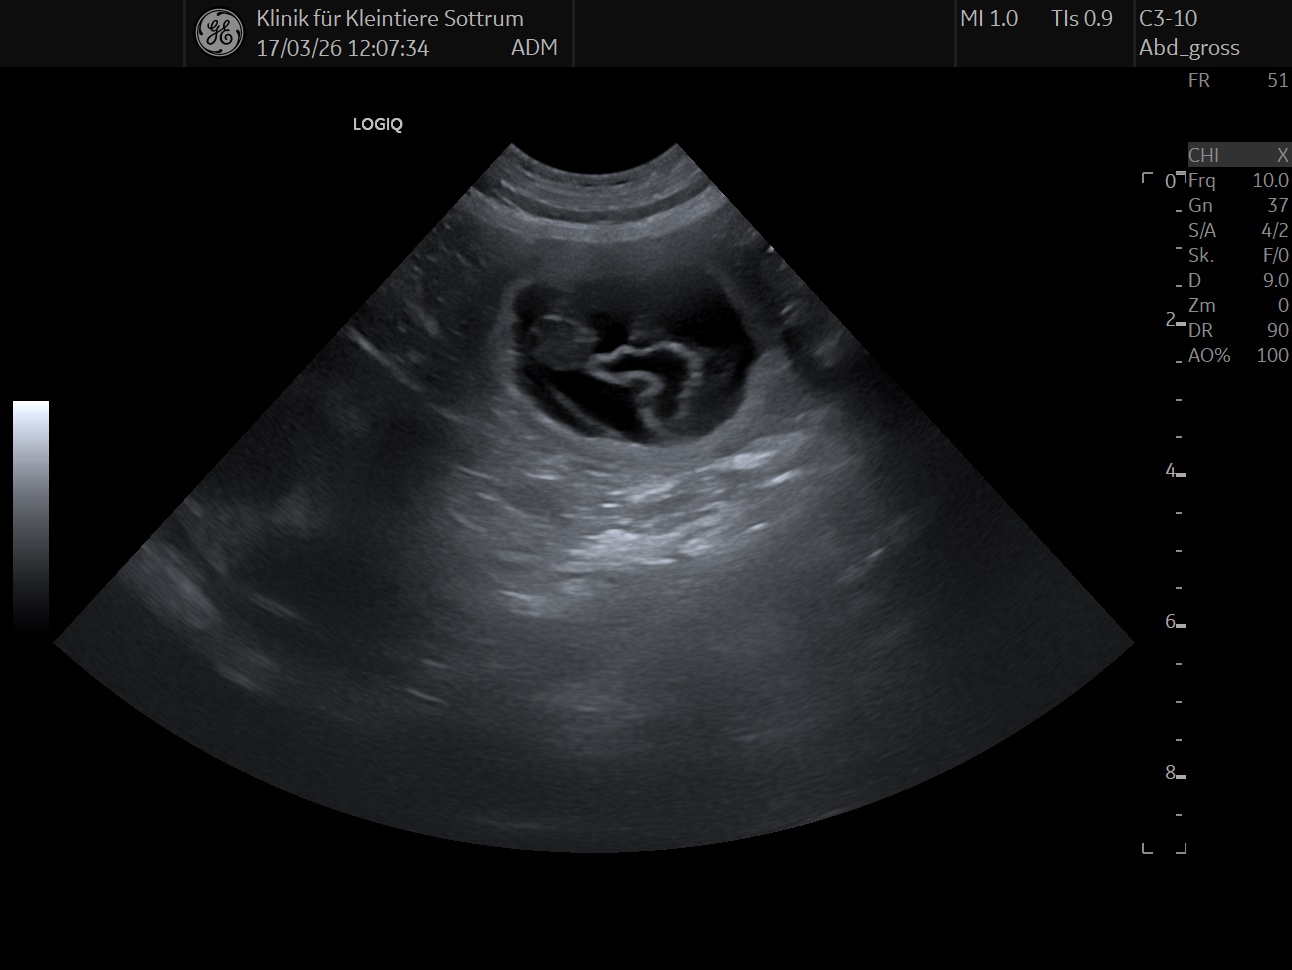

Leos im Anmarsch

17.03.2026

Daumen drücken. Wir hoffen Ende April wieder einen Wurf zu haben.